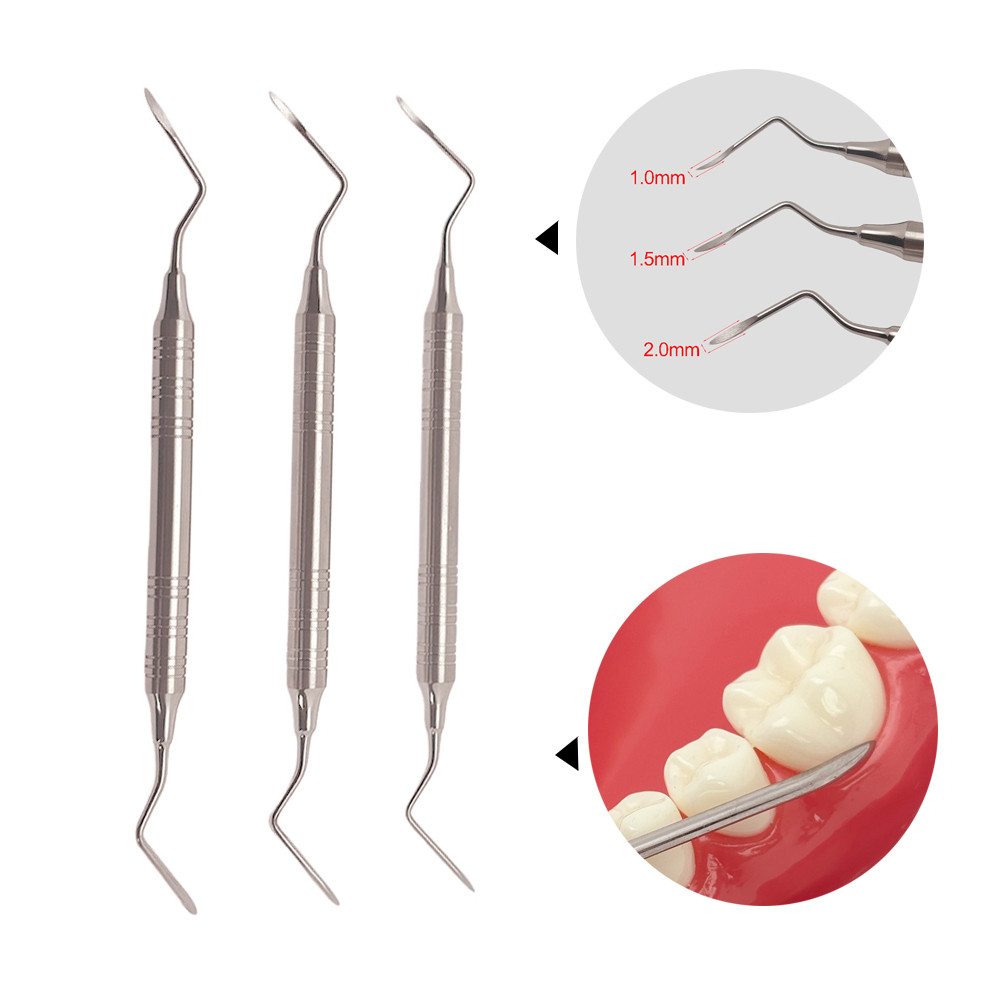

3 Variations Available

Dental Minimally Invasive Extraction Tool Root Tip Pick Elevator with Sharp Tip for Dental Implant Tooth Extraction Surgical